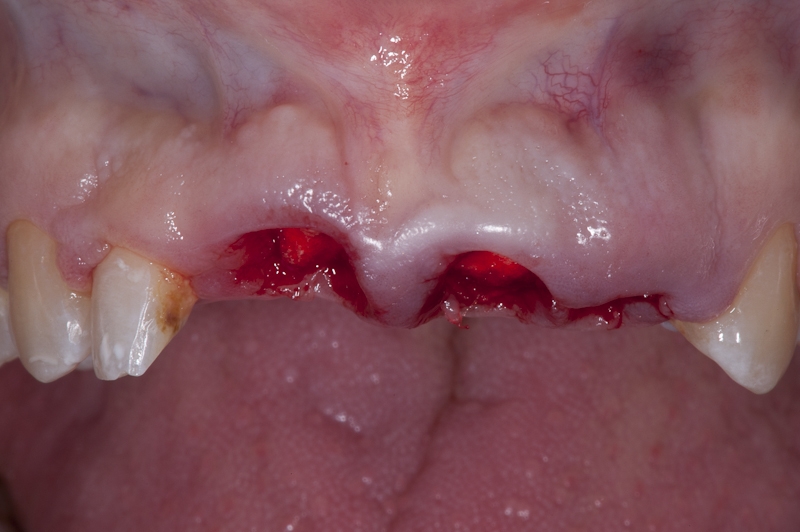

Socket preservation with permamem® - Dr. R. Rannula

Situation after tooth extraction.